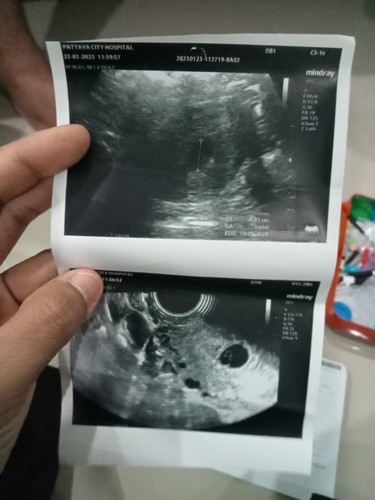

สรุป😭แท้งคุกคามค่ะ ถ้าน้องไม่แข็งแรงไม่ปกติ หมอจะยุติการตั้งครรภ์ค่ะ เจาะเลือด เรียบร้อย ฟังผลพรุ่ง

นี้ อัลตราซาวด์หน้าท้อง เจอถุง ไม่เจอเด็ก อัลตราซาวด์ช่องคลอด ไม่เจอน้อง ไม่ได้ยินเสียงหัวใจ #ทำใจไว้แล้วค่ะ ว่าน้องไม่แข็งแรง #คุณแม่ท้อง4

ตอนนี้ ร้องไห้ไม่หยุดเลยครับ แฟนดูใบอัลตราซาวด์ แล้วร้องไห้ตลอดเลย ข้าวก็ไม่กิน